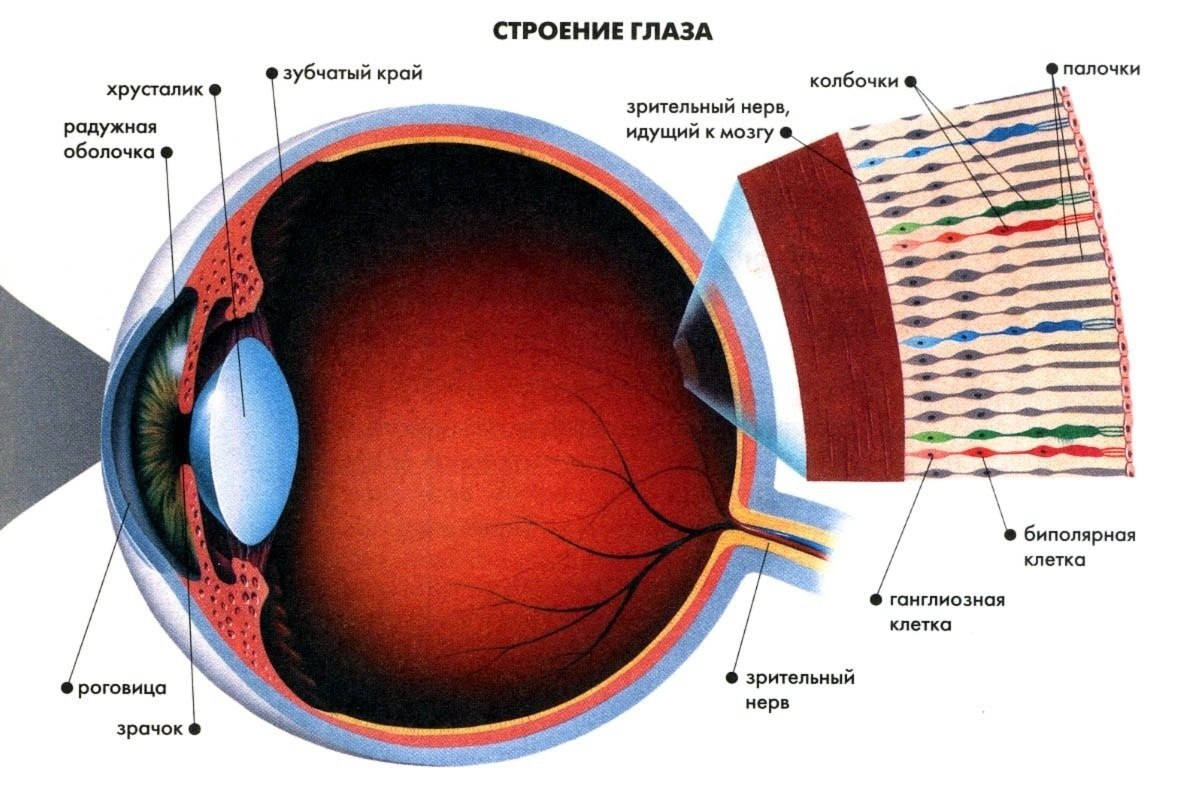

Изображения и анатомия сетчатки глаза

Раздел: Визуальный дайджест